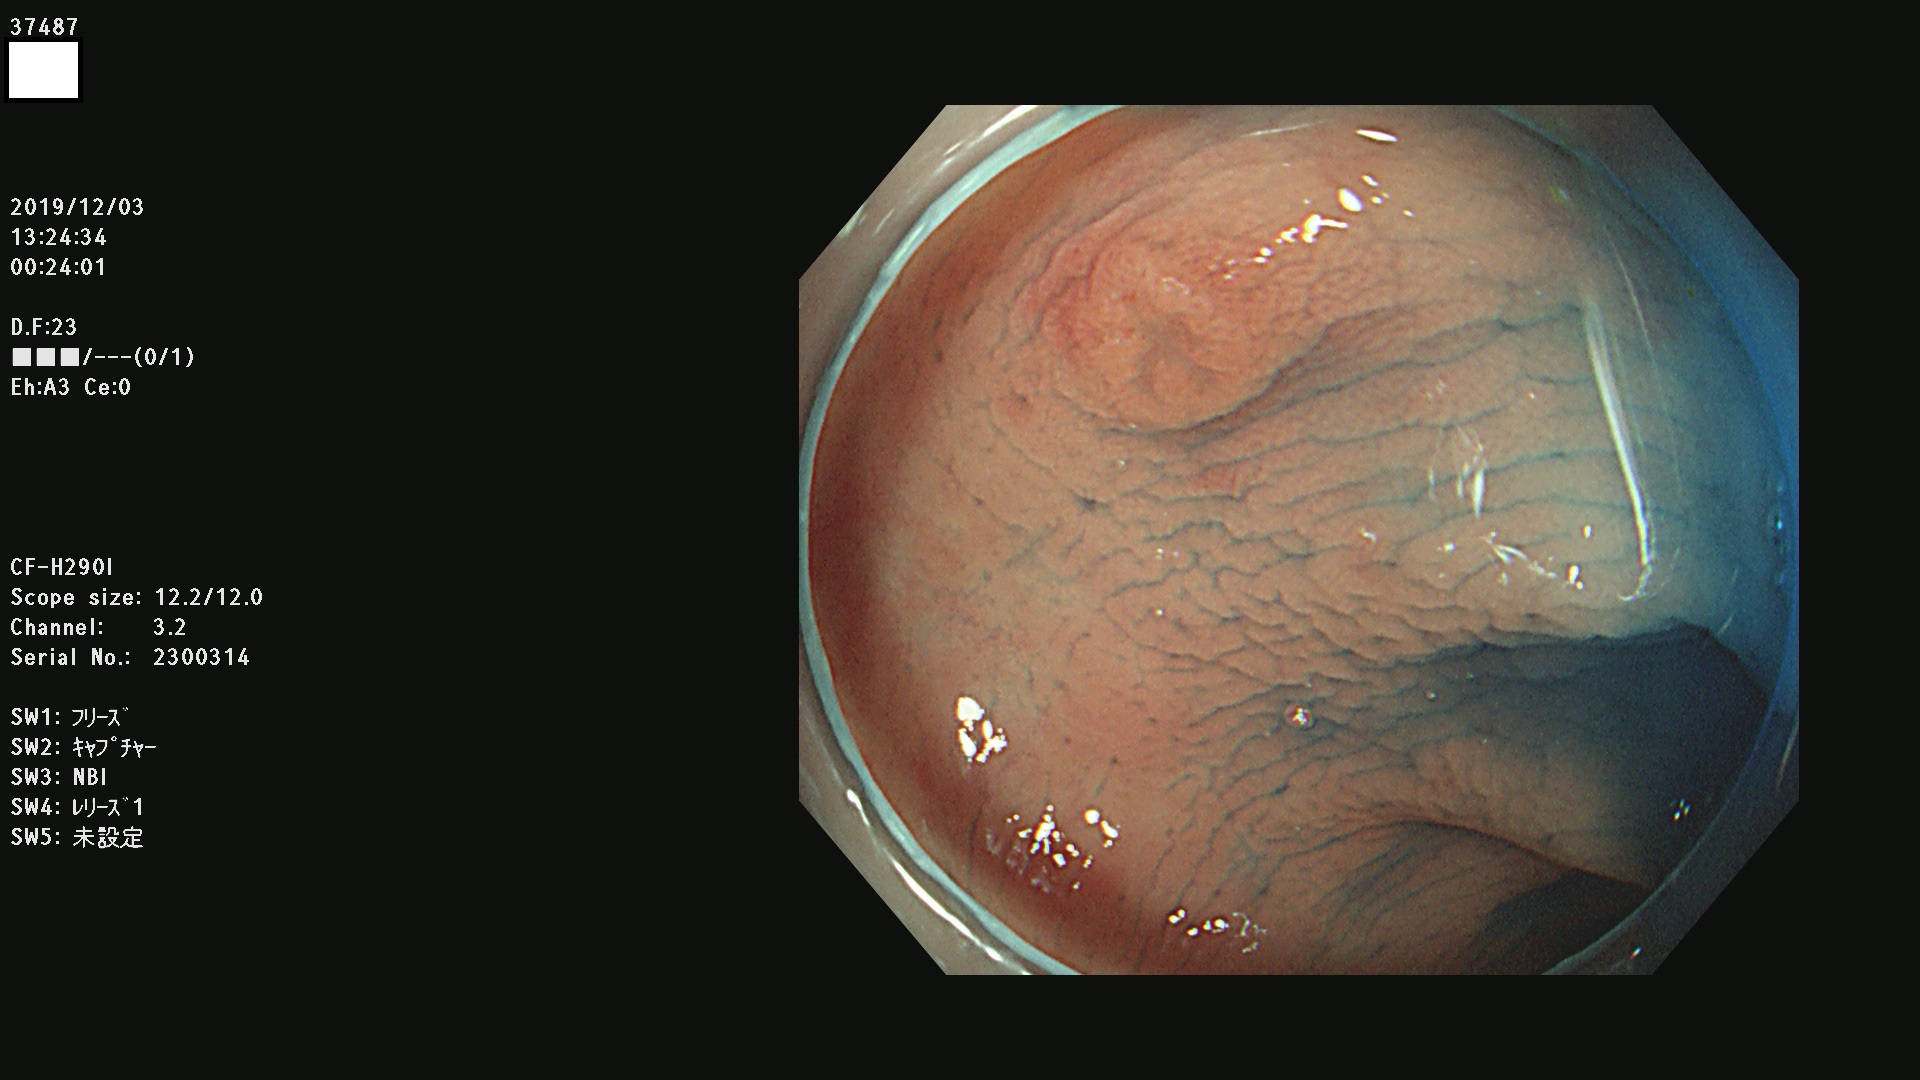

37400(SSAPのみ) 37401 37403 37404 37405 37406 37407 37408 37410 37411 37412 37413 37415 37416 37417 37420 37423 37424 37425 37426 37428 37430(SSAPのみ) 37432 37433 37434 37435 37436 37437 37438 37439 37440 37442 37443 37444 37447 37448 37449 37450 37451 37452 37455 37456 37457 37458 37459 37460 37461 37462 37464 37467 37468 37469 37470(SSAPのみ) 37471 37472 37474 37476(SSAPのみ) 37477 37478 37480 37481 37482 37483 37485 37486 37487 37488 37489 37490 37491 37492 37493 37494 37497 37499

発見困難で危険性の高い平坦型病変(上記100名より抽出)